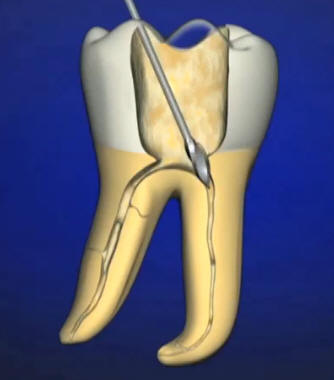

• E: Conformación del acceso a los conductos en el tercio coronal con fresas de Gates Glidden.

El resultado final debe ser una cavidad de acceso que permita a los instrumentos endodóncicos alcanzar los orificios de entrada de los conductos sin interferencia alguna y lo más rectilíneamente posible. Ver imágenes derecha.